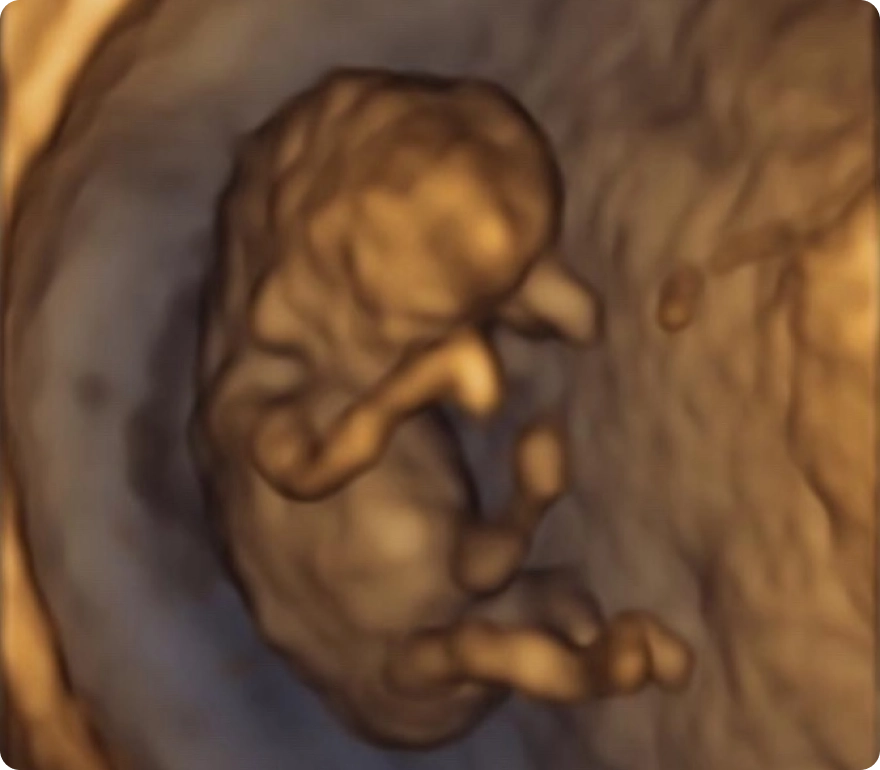

Brings images to life with real-time motion, letting you watch your baby smile, yawn, or move inside the womb.

HD

Advanced technology with stunning clarity, color, and detail—offering the most realistic, lifelike view of your baby before birth.